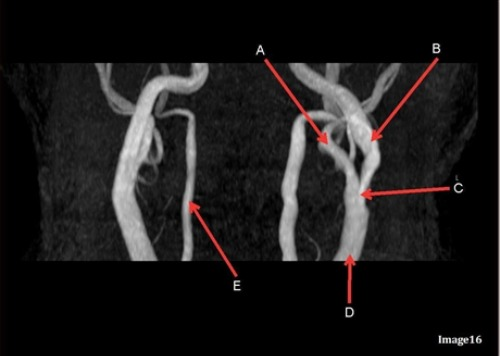

Letter A in Image 16 is responsible for blood supply to the:

C. Face

Letter D in Image 16 is pointing to:

D. Common carotid artery

Image 16 is an example of what type of MR image?

D. MRA extracranial circulation

Letter E in Image 16 is responsible for blood supply to the:

B. Posterior brain

Letter B in Image 16 is responsible for blood supply to the:

A. Anterior brain

Letter A in Image 16 is pointing to:

B. External carotid artery

Letter B in Image 16 is pointing to:

A. Internal carotid artery

Letter C in Image 16 is pointing to:

Letter E in Image 16 is pointing to:

C. Vertebral artery